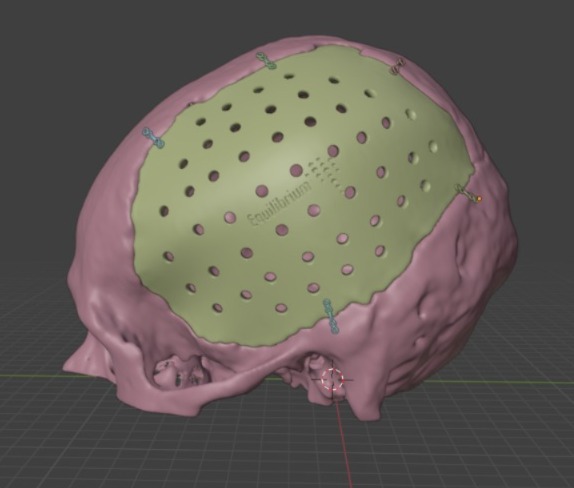

Tecnologías de Fabricación

Los implantes personalizados pueden ser fabricados mediante diferentes tecnologías y en distintos materiales, según el requerimiento del cirujano y la complejidad del diseño.

Diseño a medida

Cada implante se fabrica adaptado a la anatomía específica del paciente, mejorando la precisión y el resultado clínico.

Impresión 3D personalizada

A través de tecnología aditiva desarrollamos implantes personalizados, ofreciendo una solución a medida para cada paciente.

Variedad de Materiales

La prótesis personalizada puede fabricarse en diferentes materiales, seleccionados según el uso clínico, la región anatómica, las dimensiones del implante y los requerimientos específicos del cirujano. Cada caso es evaluado de manera individual para garantizar seguridad, funcionalidad y durabilidad.

Fabricamos implantes en titanio, cromo cobalto, PMMA, cerámica bifásica, hidroxiapatita y PEEK, todos seleccionados según la indicación médica y el tipo de procedimiento quirúrgico.

Captura y Modelado 3D

La reconstrucción anatómica se realiza a partir de imágenes obtenidas mediante técnicas de diagnóstico como Tomografía Axial Computada (TAC) o Resonancia Magnética (MRI). Estas imágenes son procesadas con software especializado para modelar en tres dimensiones cualquier región anatómica, incluso con patologías complejas.

Inclusión de Implantes

En el modelado digital 3D se pueden incluir implantes ortopédicos como placas, tornillos, mallas, prótesis y otros dispositivos, diseñados en tamaño real y en relación directa con la anatomía del paciente. Esto permite simular distintos escenarios quirúrgicos antes de la cirugía.